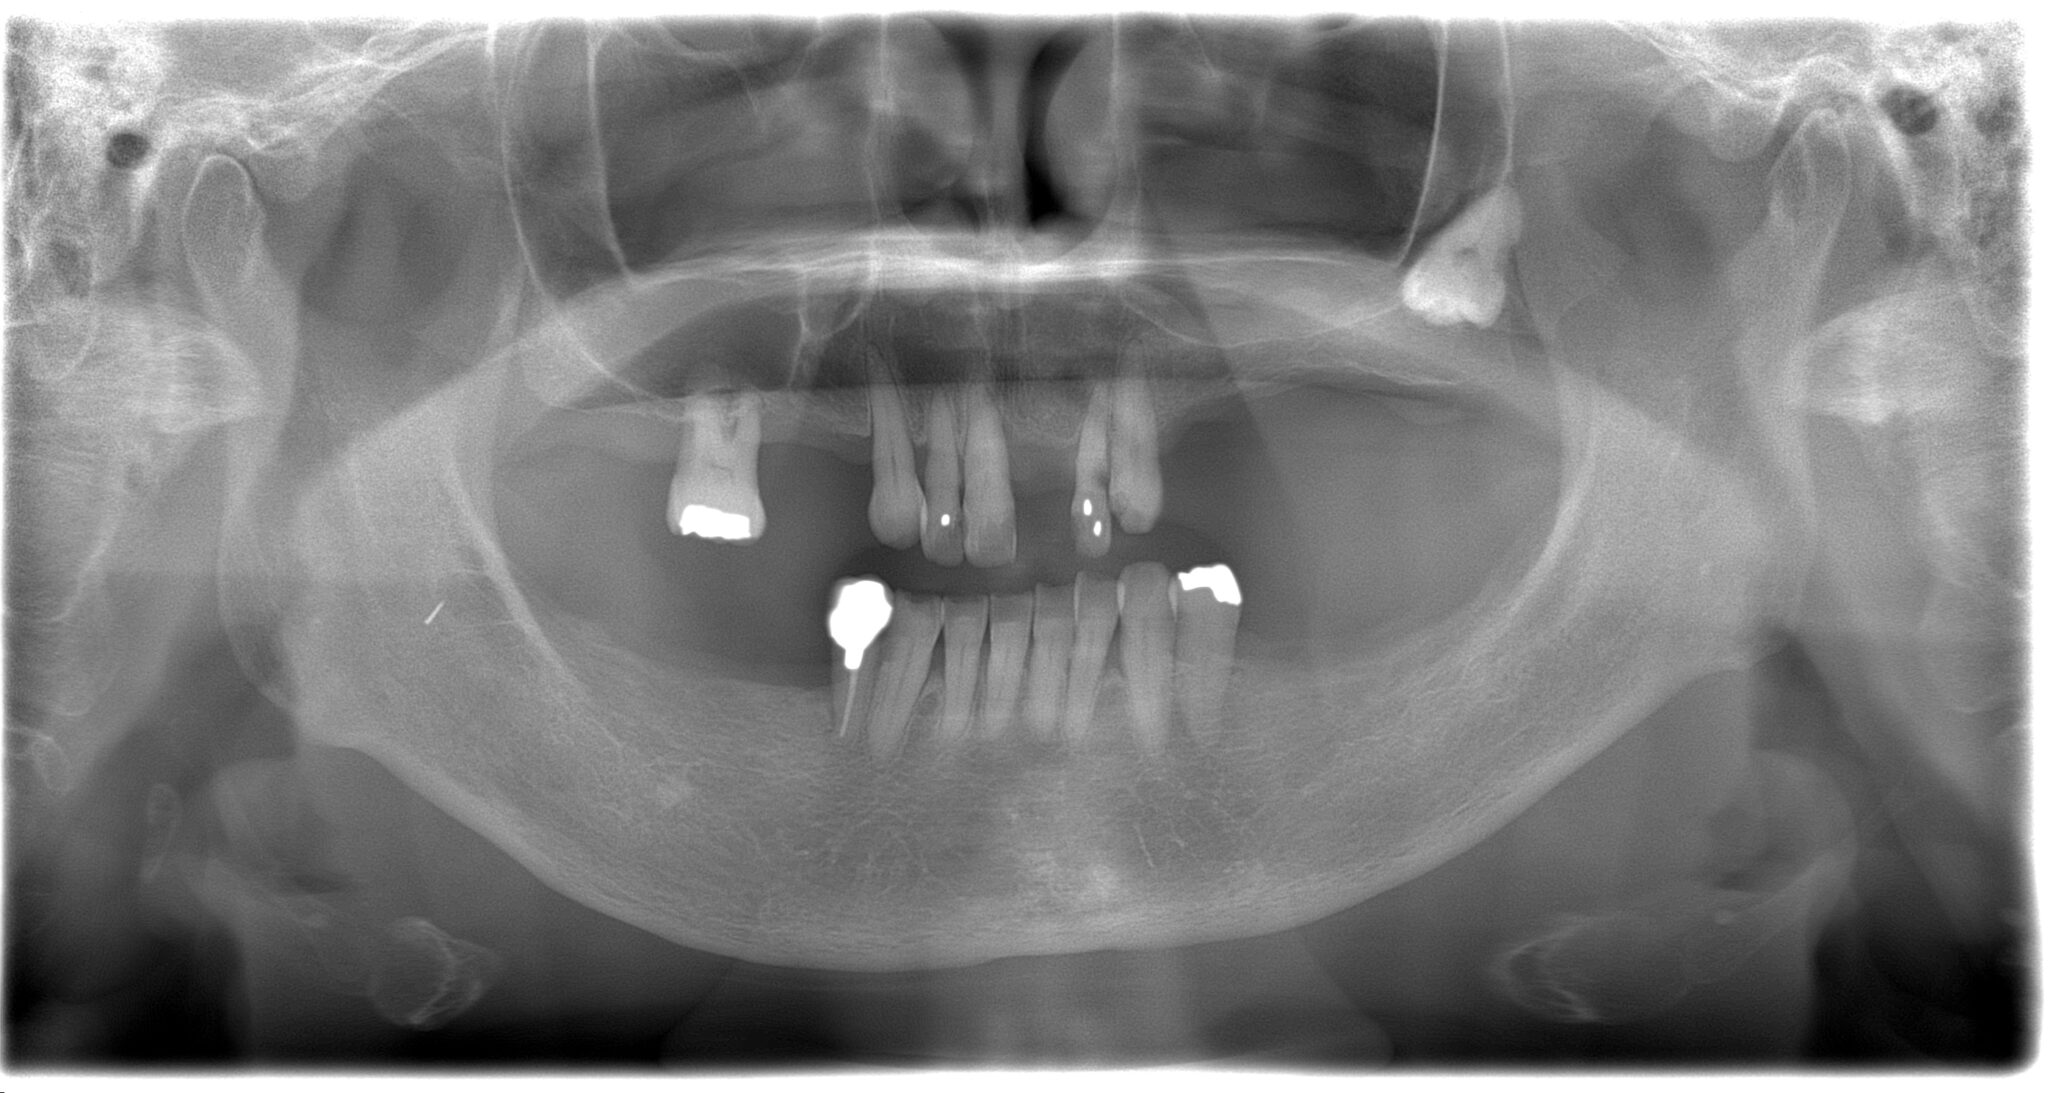

| 診断名・ 主な症状 |

臼歯部欠損 |

| 治療内容 | インプラント埋入(左下5・6,右下5・6,左上4・6) サイナスリフト(左上4・6) ジルコニアBr(右上6−左上3) E –MAX CAD(右下4) セラミックインレー(左下4) |